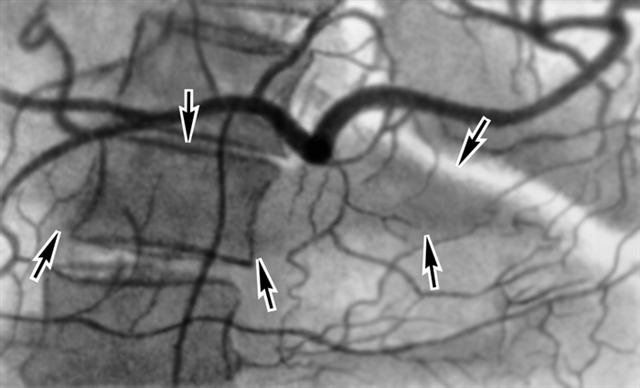

Рис. 3. Целиакограмма при хроническом панкреатите: отмечается увеличенная поджелудочная железа (указана стрелками) с усиленным кровоснабжением.